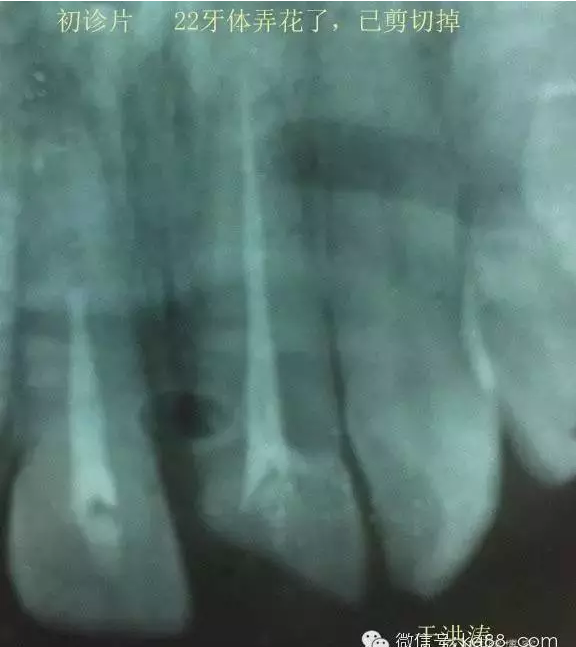

檢查:明顯可見22牙冠橫向斷裂至頸1/3處,近遠中與腭側(cè)斷裂至齦下??梢?/span>11牙冠斜向近中斷裂,近中與腭側(cè)均斷裂至齦下。21牙冠中1/3有裂痕。11 21 22松動(0),11 21叩(+),22叩(-),11 21 22探(-),11 21 22冷熱(-)。11 21 22唇側(cè)牙齦與粘膜和根尖相應(yīng)部位未見明顯改變。11 22腭側(cè)牙齦增生性改變。11 21 22腭側(cè)粘膜和根尖相應(yīng)部位未見改變。11 21 22舌側(cè)窩均有充填物。面部左右對稱無改變。余牙正常。(11,21,22牙冠顏色無改變)。

輔助檢查:X線片檢查11 22牙冠均有缺失。11 21 22 髓腔內(nèi)均有充填物,11充填不到位, 21充填不實,22充填到位髓腔高密度影像。11 21 牙周膜有增寬,21根尖區(qū)有2mm左右低密度影像。未發(fā)現(xiàn)有牙根側(cè)穿或斷裂異物。

診斷:11,21慢性尖周炎,11,22殘冠。